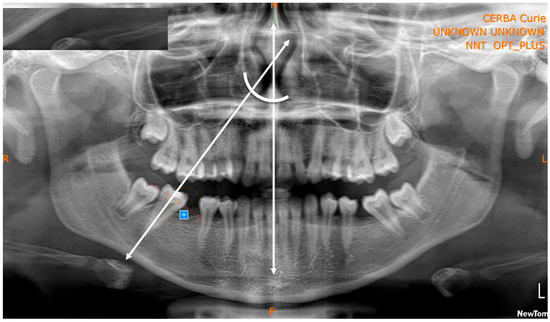

Spontaneous Second Molar Migration After MIH-Affected First Molars Extraction: A Radiographic-Based Method Evaluation

by Santo Andrea Stabilini, Lucia Giannini, Niccolò Cenzato, Francesca Olivi Mocenigo, Claudia Salerno, Cinzia Maspero and Maria Grazia Cagetti

Children 2025, 12(12), 1589; https://doi.org/10.3390/children12121589 - 23 Nov 2025

Background: Molar–incisor hypomineralization (MIH) represents a challenging dental condition, often requiring complex and invasive interventions. In severe cases, extraction of the first permanent molars (FPM) is frequently indicated. However, methods to assess the effectiveness of this approach in promoting spontaneous mesialization of the second permanent molars (SPM) through Orthopantomography (OPT), as well as the factors influencing this process, remain unexplored. Aim: This perspective study aimed to assess the effectiveness of novel radiograph-based methods for assessing spontaneous SPM mesialization after FPM extraction and to identify clinical and developmental factors associated with complete space closure. Methods: OPTs of 19 patients (12 males, 7 females; age range 6.2–13.8 years) who underwent extraction of 36 FPM due to severe MIH were analyzed by 2 operators. Pre- and post-extraction OPTs were evaluated using specifically developed geometric measurements of distances and angles to quantify SPM movement. Variables considered included patient age at extraction, dental developmental stage (Demirjian index), observation period, and presence or absence of the third permanent molar (TPM). The reliability of the proposed measurements evaluated through ICC (Intraclass Correlation Coefficient) resulted in values above 0.9, confirming excellent intra- and inter-operator reliability. Results: Complete or quite-complete mesialization (target scores 0–1 and ≤33% residual space) occurred in 78.6% of maxillary and 73.7% of mandibular sites. Maxillary SPMs showed more favorable spontaneous movement, exhibiting substantial uprighting (e.g., from −32° to 2°) and a higher frequency of complete or near-complete space closure (78.6% vs. 73.7% in the mandible). Developmental stages D–E of SPM were associated with successful outcomes. Conclusions: Early extraction of severely compromised first permanent molars (FPMs) can represent an effective treatment option to promote spontaneous mesialization of SPMs, particularly in the maxilla. The proposed radiograph-based measurement method demonstrated high consistency and reproducibility. Overall, this novel measurement approach may serve as a reliable and valuable tool for future clinical and research applications. Full article

Figure 1